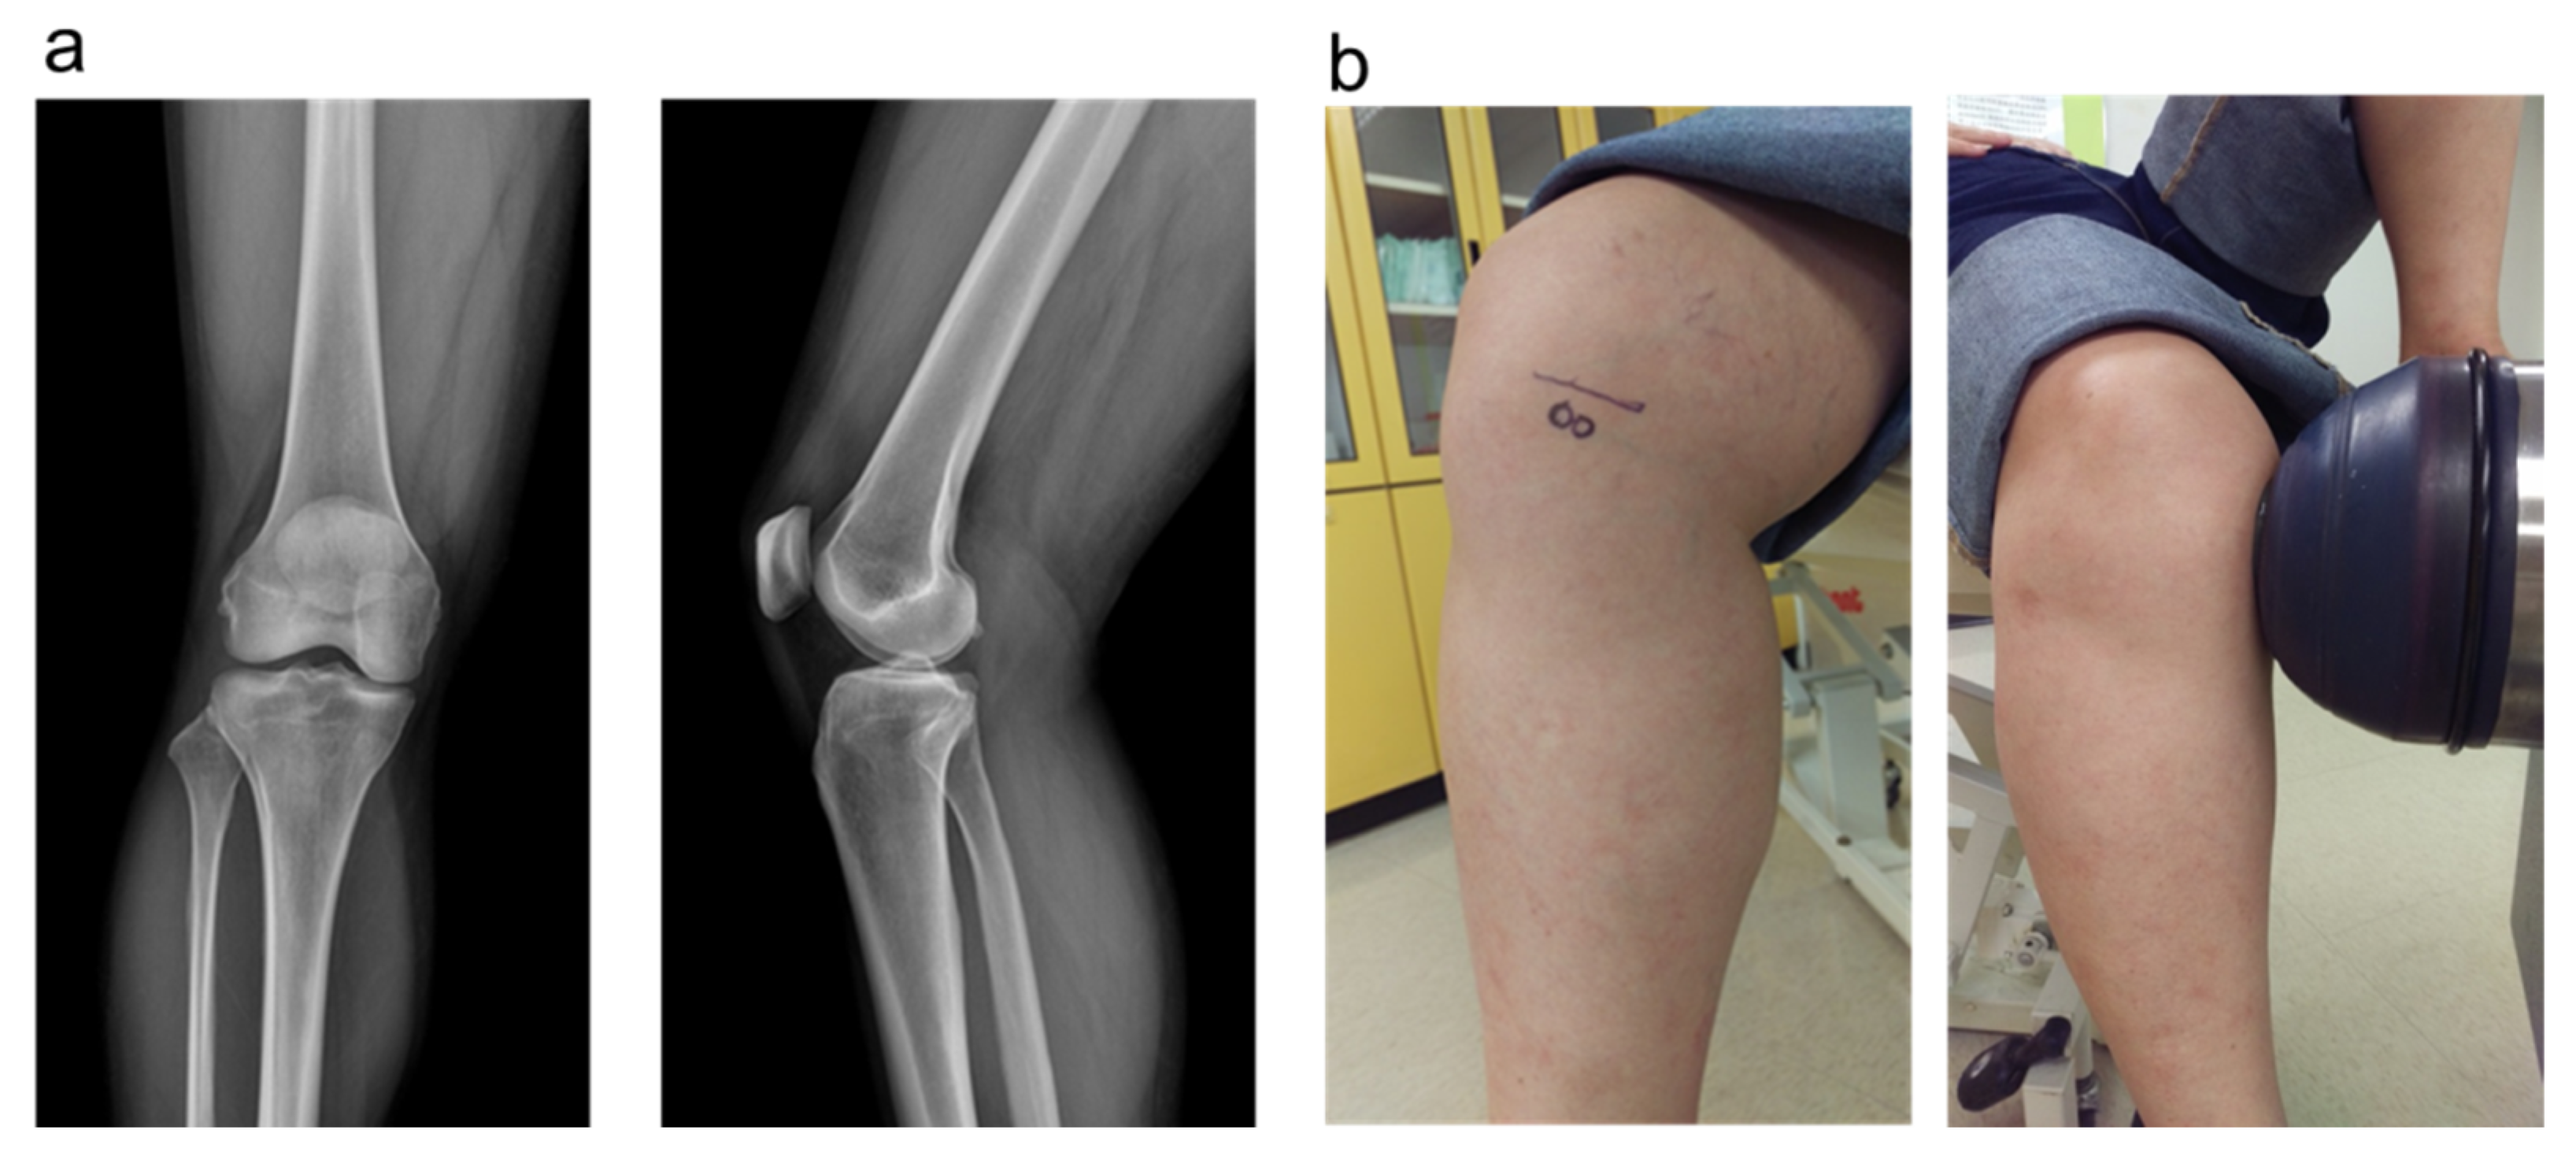

2.5. The Plain Radiographies and MRI

2.6. Shockwave Application